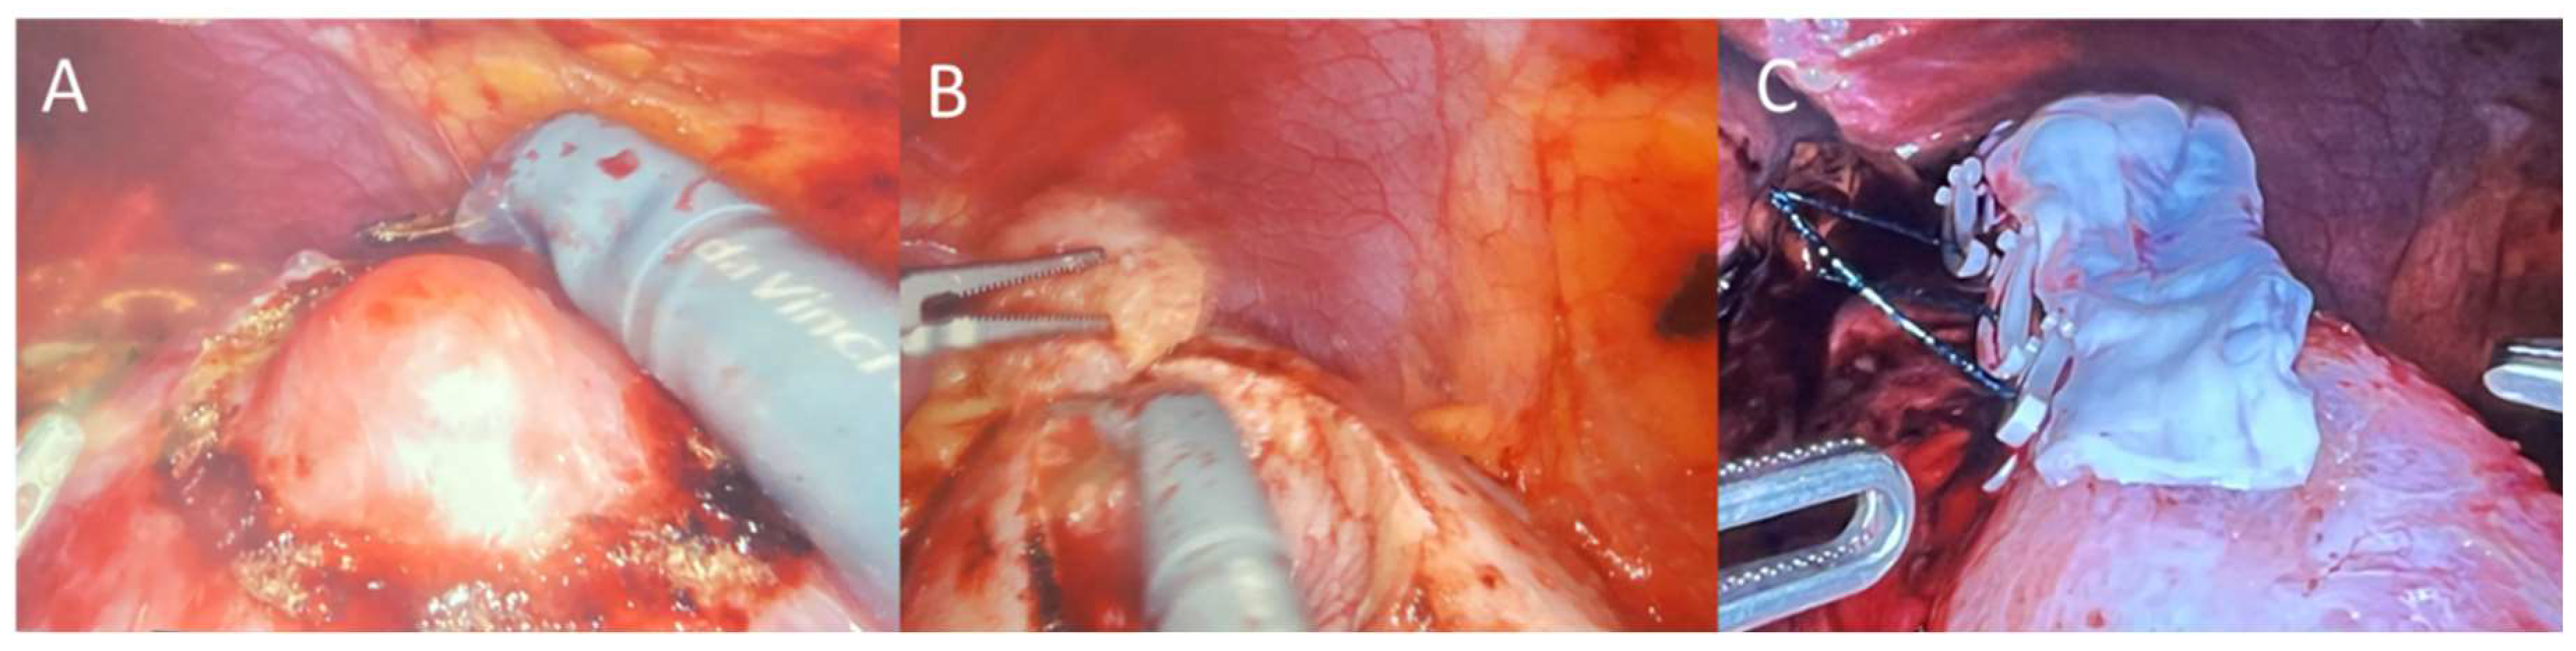

All partial nephrectomy procedures were performed by one surgeon using the four-arm da Vinci surgical system (Intuitive Surgical; Sunnyvale, CA, USA) using a similar technique for each patient as previously described.[14] In brief, the patient is placed in the flank position, table is flexed, insufflation is performed, robotic trocars are placed (shifted laterally for obese patients), colon was reflected to allow access to retroperitoneum, peritoneum was incised, blunt dissection was performed to locate and expose the diseased tissue on the kidney, the area around the tumor was marked circumferentially by cautery, ultrasound and indocyanine green were used to confirm the tumor margin was appropriately demarcated, renal artery was clamped, tumor was excised, parenchymal defect was closed every 1 cm with 3-0 sutures with a clip to sandwich close the renal parenchyma for hemostasis, and artery was unclamped. A 6x3 cm pre-hydrated AM graft (BioTissue, Miami, FL, USA) was then taken from its sterile packaging under strict aseptic conditions and rinsed with saline, introduced through the 12mm trocar, placed over the renal incision as a barrier with Small Graptor (grasping retractor) and ProGrasp forceps (Intuitive Surgical; Sunnyvale, CA, USA), and secured in place using fibrin hemostat spray (Figure 1). Diseased renal tissue was extracted, drain placed, trocars removed, and wounds were closed with sutures.

Figure 1. Representative surgical technique of demarcating the renal tumor with cautery (A), excusing the tumor (B), suturing close and applying AM over the renal incision (C).